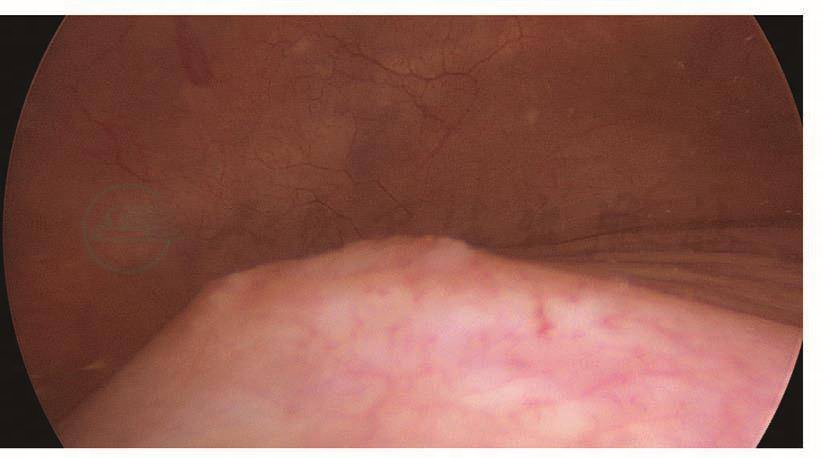

如果术中无法确认输尿管是否损伤,可以考虑在结束手术前进行膀胱镜检查,观察输尿管出口的喷尿情况。膀胱镜下先找到膀胱黏膜,在膀胱底部找到突出的部位,此处即为膀胱三角区,输尿管出口位于其两侧。有时候输尿管蠕动的间隔比较长,必要时可以静脉注射呋塞米20mg,促进输尿管蠕动、喷尿。如果观察到两侧输尿管出口正常蠕动并有喷尿,说明输尿管没有断裂性损伤,但不能排除热损伤(图117~图120)。

图117 膀胱三角区

图118 左侧输尿管出口

图119 右侧输尿管出口

图120 输尿管出口喷尿